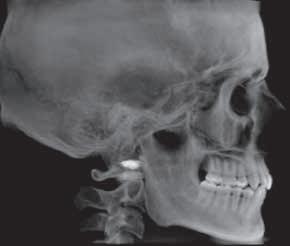

Oral manifestations of pemphigus vulgaris include bullous lesions, erosions with ragged borders, desquamative gingivitis and a positive Nikolsky’s sign (Figures 7,8). Multiple large lesions on the skin can result in fluid loss, electrolyte imbalance, septicemia, and death.

Diagnosis of pemphigus vulgaris is determined by routine histology and direct immunofluorescence following biopsy. Treatment of minor lesions confined to the oral mucosa may initially be managed with topical and/or systemic steroids; however, patients often require other systemic immunosuppressants or biologics. A team approach to treatment including both dentists and physicians is required.

Figure 6. Symblepharon (scar) in a patient with MMP extending from the conjunctiva to the eyeball. Figures 7 and 8. Erosions with ragged borders seen with pemphigus vulgaris. Figure 7 Figure 8